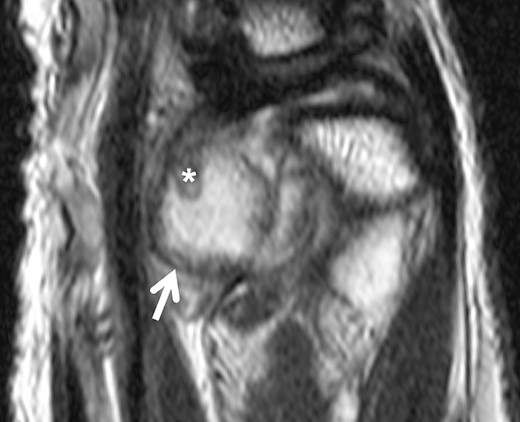

MRI scan revealed suspicion of ganglion cyst formation. The images (Figs 1 and 2) depicted a palmar-directed mass originating from the DRUJ with a transverse diameter measuring a maximum of 12 x 17 mm. The mass exhibited a predominant fluid isointense internal signal, accompanied by marginal signal depressions on T2-weighted sequence. These depressions within the suspected ganglion raised suspicion of diffuse-type tenosynovial giant cell tumor. The mass had contact to the flexor tendons at the level of the DRUJ. No pathological bone marrow edema was observed.

Sagittal slice of a T2-weighted fast-spin echo sequence of the DRUJ—well-defined hyperintense lesion on the volar aspect of the DRUJ; capsular blooming artifact (short arrow); hypointense, internal structure within the distended DRUJ (asterix), chondromatosis foci accordingly.